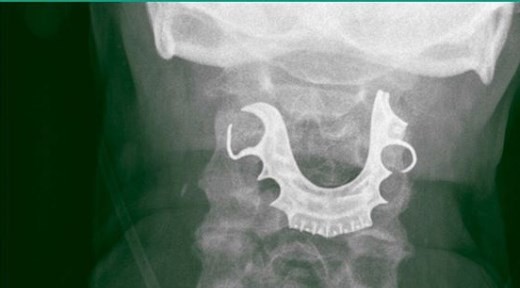

Un hombre de 72 años tuvo que ser intervenido quirúrgicamente debido a que, durante una operación, se tragó la dentadura postiza, la cual quedó atascada en la faringe.

El individuo permaneció con la placa durante ocho días en la garganta, hasta que finalmente una radiografía dio con el problema que le generaba dolor y sangrado.

Tras ser dado de alta, a los seis días regresó al médico debido a las constantes molestias, como dolor en el cuello, sangrado y dificultad para tragar. Sin embargo, los especialistas señalaron que se trataba de una infección respiratoria, por lo cual le diagnosticaron antibióticos.